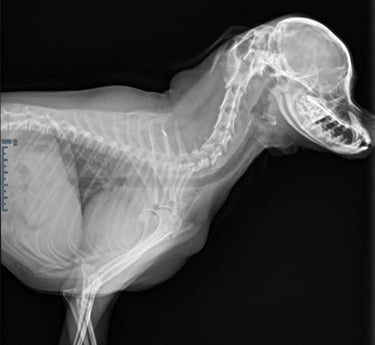

Radiografie (RX)

Consult op de praktijk of aan huis

Een RX is geschikt om botbreuken, een longontsteking, de hartgrootte, arthrose,....op te sporen.

Als de hond - kat niet lang genoeg stil kan blijven liggen dan is een verdoving noodzakelijk. Voor RX van het heupgewricht is een volledige verdoving noodzakelijk.